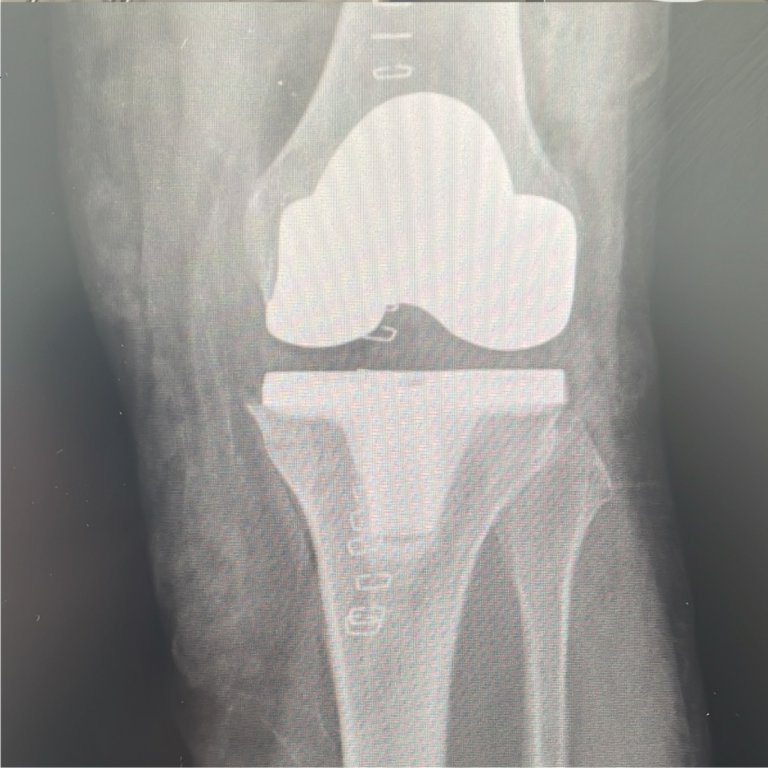

Chirurgia robotica nella protesi di ginocchio